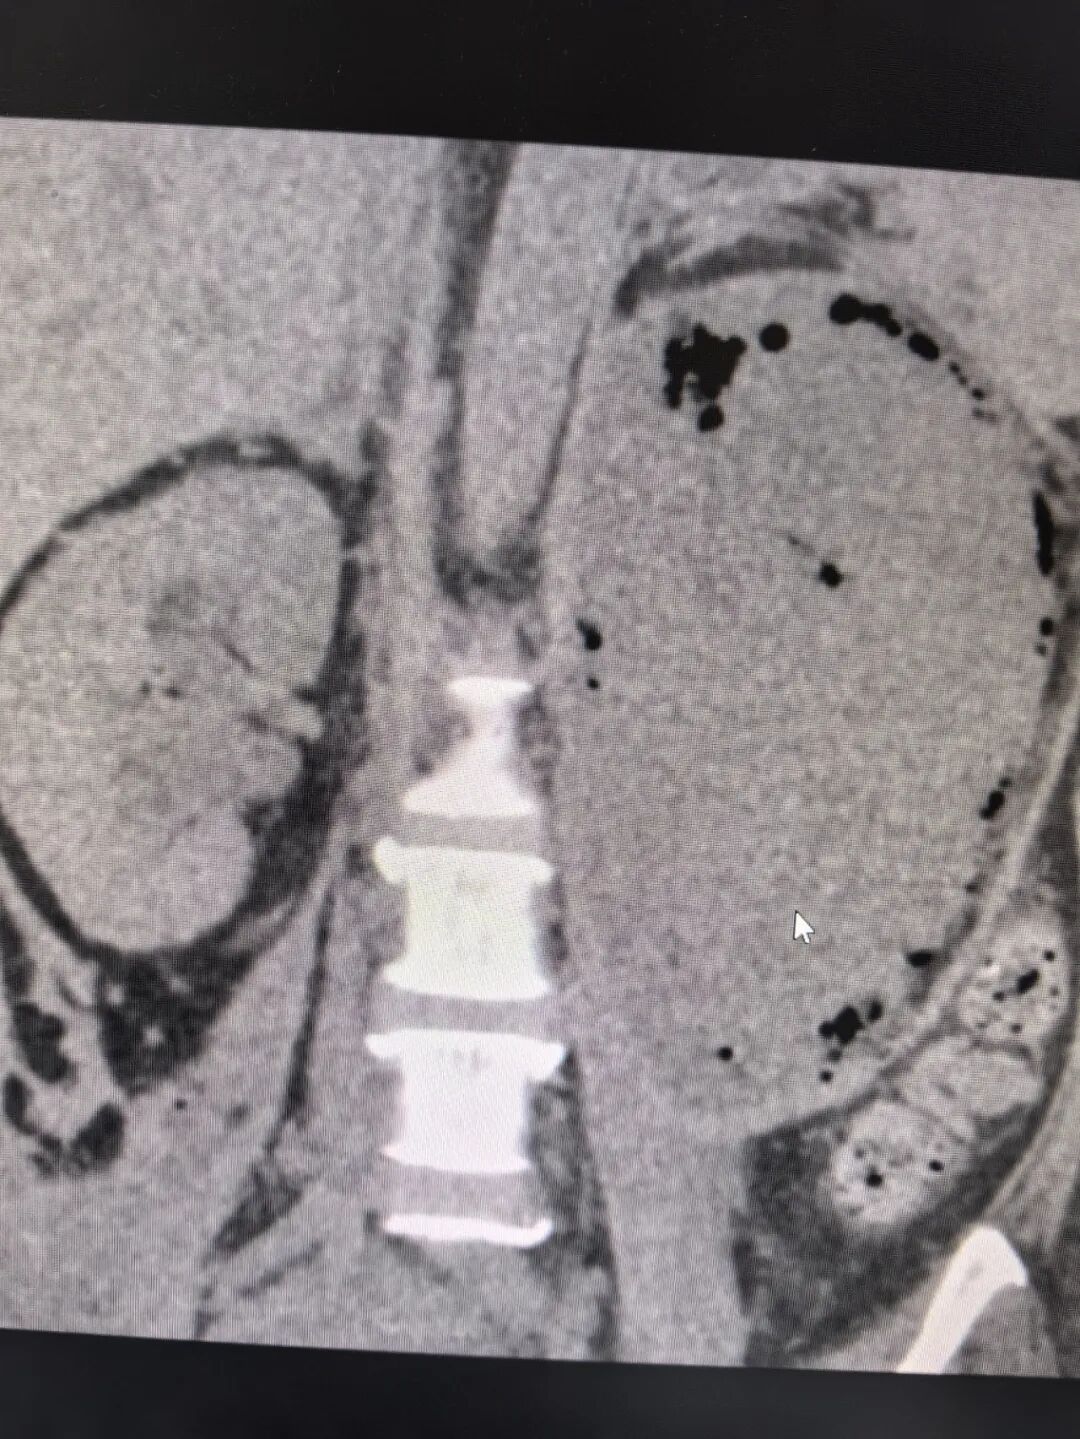

谢庆祥教授接诊后,对患者进行了全面而详细的检查。患者腹部CT见左肾积气严重、左肾大部分毁损、左肾盂内可疑内容物、右肾盂积水、腹膜后炎性积液致双侧输尿管腹段粘连、压迫。此外,患者还有双侧胸腔积液、肺部感染、肾功能不全、糖尿病、重度贫血、低蛋白等病症。进一步完善双肾CT增强检查,提示左肾多处脓肿伴积气,左肾实质毁损严重,左肾增强显影不理想。